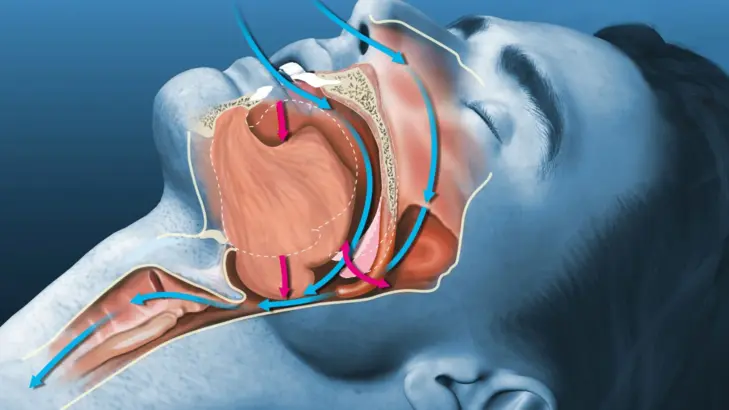

توقف التنفس في النوم: الخطر الذي لا تشعر به

يؤكد أي خبير في علاج اضطرابات النوم أنَّ أكثر ما يُقلق ليس ما يشعر به المريض؛ بل ما لا يشعر .. المزيد